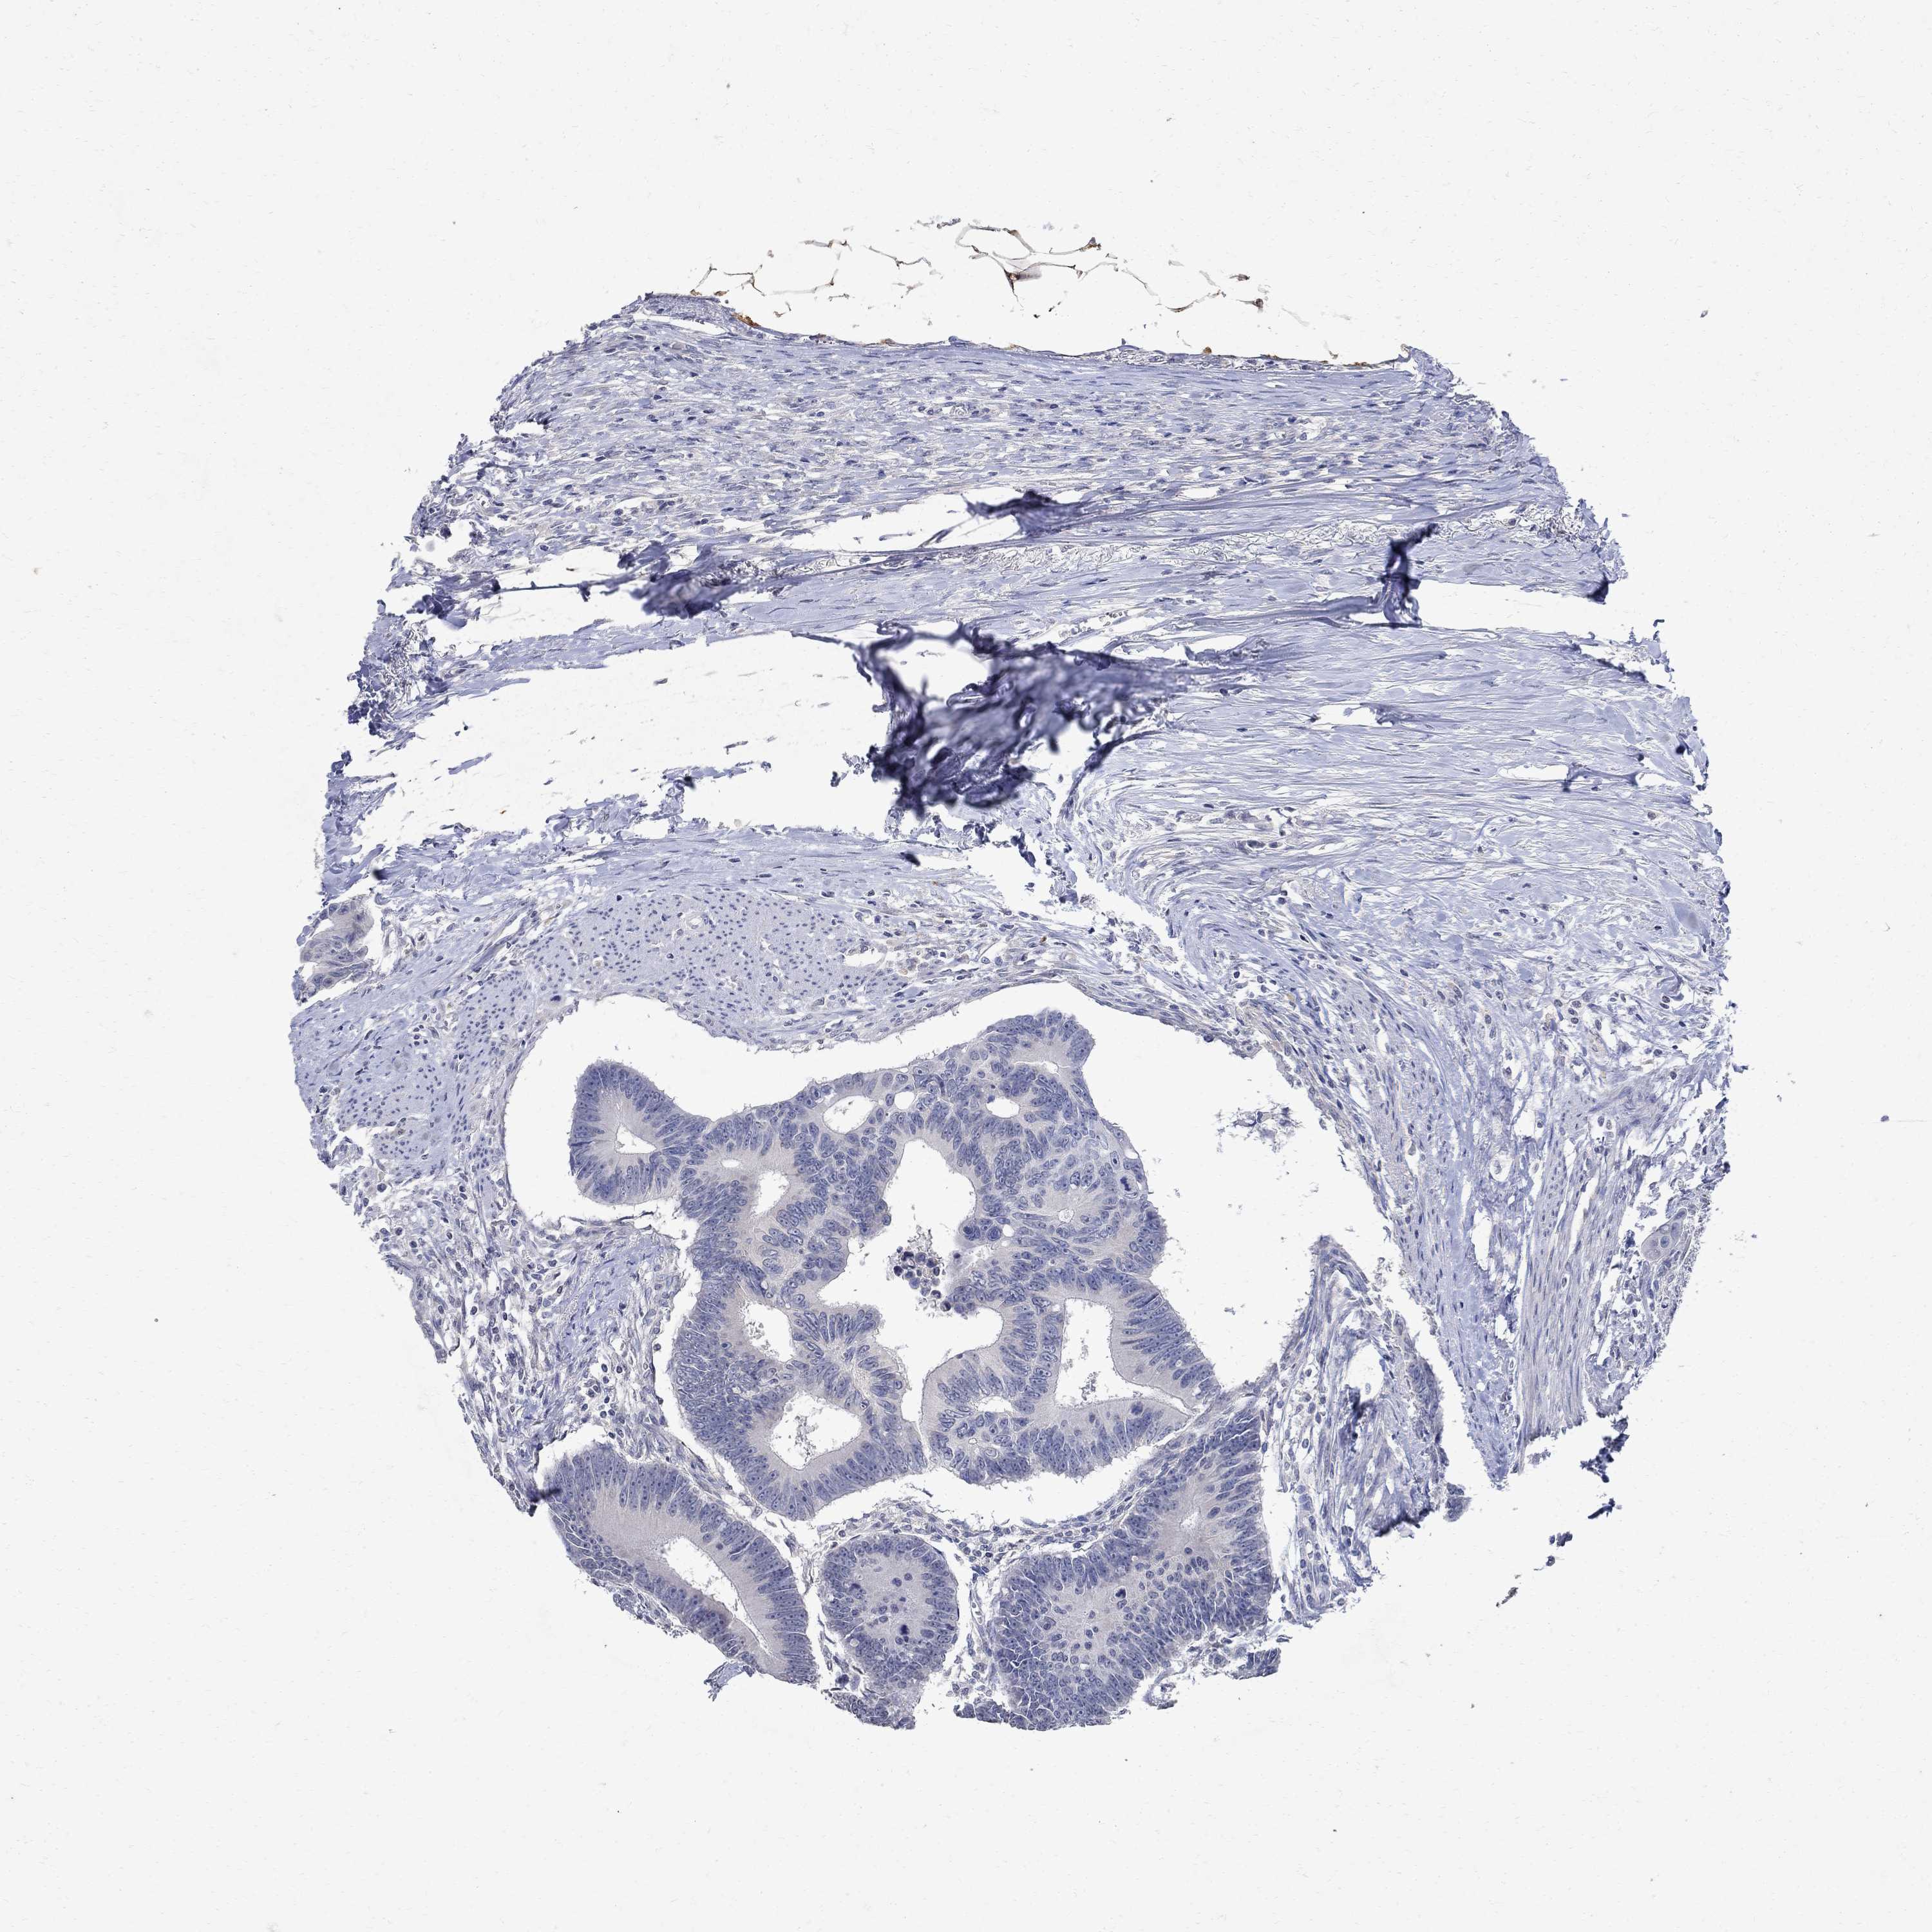

CANCER COLORECTAL CANCER Show tissue menu

Colorectal cancer

Human cancer

Colon adenocarcinoma

RECTUM ADENOCARCINOMA (TCGA) - Interactive survival scatter ploti

TMEM169 is not prognostic in Rectum Adenocarcinoma (TCGA)